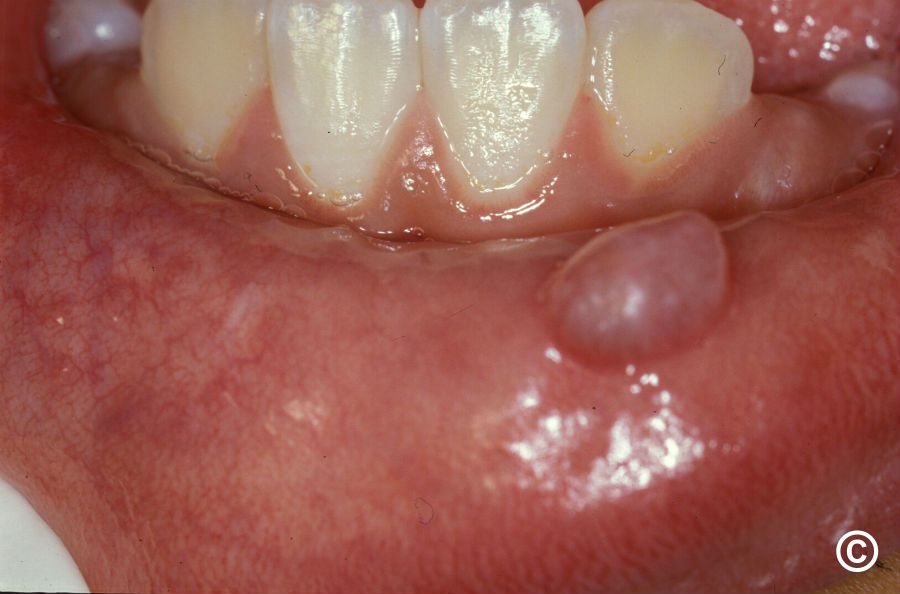

💧 Mucoceles

- Form in soft tissues — lip, cheek, or tongue

- Visible as soft, clear or bluish bumps

- Usually painless unless irritated

- Often appear suddenly after biting lip or cheek

- May rupture and refill repeatedly

- Small ones may resolve; persistent ones need removal

- Visible bump: Soft, round, bluish or clear bump on the lip, cheek, or tongue